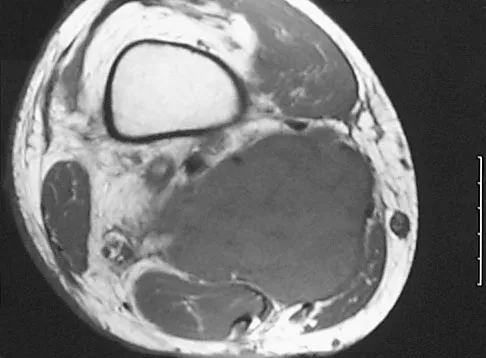

A 35-year-old woman states that she stepped on a piece of glass 6 months ago and reports numbness and shooting pain along the plantar lateral forefoot. She had previously received steroid injections in the 3 to 4 webspace. Examination reveals mild tenderness along the plantar fascia; no Tinel's sign is noted plantar medially and no Mulder's click is noted distally. An MRI scan is shown in Figure 7. What is the most likely cause of the numbness?

Explanation

The MRI scan reveals a laceration through the abductor hallucis musculature and lateral plantar nerve, producing numbness along its distribution. There is no evidence of a foreign body on the MRI scan. Baxter's nerve, or nerve to the abductor digiti quinti muscle, is the first branch off the lateral plantar nerve and impingement of this nerve typically produces a Tinel's sign along the nerve branch deep to the abductor hallucis muscle. Interdigital neuroma would be suggested by the presence of a Mulder's click. A digital nerve laceration would exhibit isolated numbness more distally. Baxter DE, Pfeffer GB: Treatment of chronic heel pain by surgical release of the first branch of the lateral plantar nerve. Clin Orthop Relat Res 1992;279:229-236.